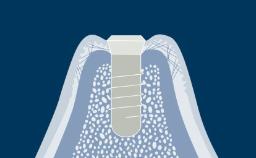

The understanding of the facial anatomy with its associated osseous and neurovascular structures is essential to the implant surgeon. During treatment planning and implant surgery, certain critical landmarks and boundaries must be respected. The anatomy of the maxilla and mandible is complex, and the implant surgeon should also keep in mind that many variations exist between individuals. The aim of this module is to review the basic anatomy of the facial region and to provide an overview of the important structures involved in implant dentistry in the average adult patient.

- describe the osseous structures of the maxilla

- describe the osseous structures of the mandible